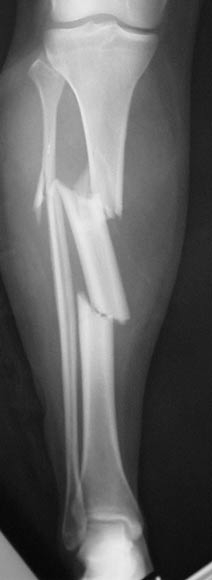

Example X-ray Images

Segmental Tibial Shaft Fracture